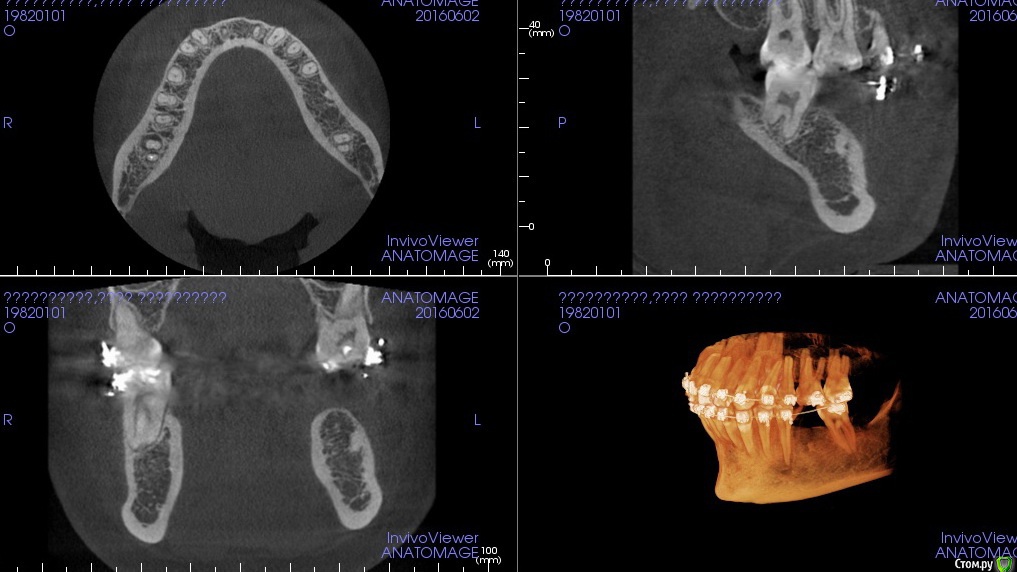

k.t.m. Опубликовано 7 июня, 2016 Поделиться Опубликовано 7 июня, 2016 коллеги, корешок ли это? Ссылка на комментарий

Astronaft Опубликовано 8 июня, 2016 Поделиться Опубликовано 8 июня, 2016 (изменено) Я думаю - корешок. Смотрите на симметричный - уровень, щечное расположение, плотность. Изменено 8 июня, 2016 пользователем Astronaft 2 Ссылка на комментарий

faity Опубликовано 8 июня, 2016 Поделиться Опубликовано 8 июня, 2016 На гиперцементоз похоже. Пародонтальной щели не прослеживается Ссылка на комментарий

Jurai Опубликовано 8 июня, 2016 Поделиться Опубликовано 8 июня, 2016 Похоже на корешок. Давеча подобное было - тоже сомневалась. Трепаном 5мм аккуратно кортикальную сняла и элеватором таки поддела. Ссылка на комментарий

kamranchick Опубликовано 8 июня, 2016 Поделиться Опубликовано 8 июня, 2016 Не похоже) голосую за гиперцементоз) да и зачем его убирать Ссылка на комментарий

Fibez Опубликовано 8 июня, 2016 Поделиться Опубликовано 8 июня, 2016 голосую "не корень" Ссылка на комментарий

red_butler Опубликовано 9 июня, 2016 Поделиться Опубликовано 9 июня, 2016 не корень Ссылка на комментарий